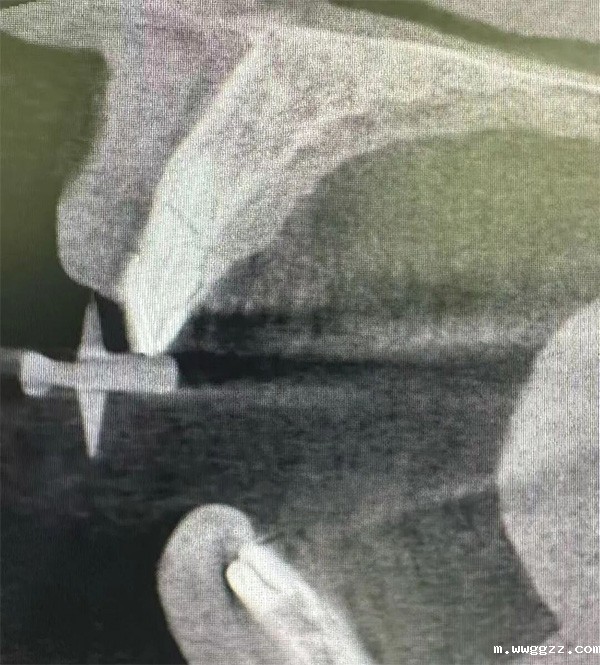

1、微创拔牙环节:运用微创牙挺与轻柔的侧方提插技术,在完全不损伤唇侧骨壁的前提下,将患牙断根整体取出,实现了“牙走骨存”的理想状态,最大程度保留了唇侧骨板的完整性,为后续种植体的植入创造了优质的生物学环境。

2、高难度即刻种植环节:在拔牙后形成的骨窝空间有限、植入角度受解剖结构限制的情况下,凭借对种植体三维位置的精准控制,巧妙利用剩余可用骨量,实现了良好的初期稳定性。该操作不仅考验术者的空间感知与手术技巧,也对种植体类型的选择与个体化植入策略提出了极高要求。手术最终成功实现了“即拔即种”的理想治疗目标,显著提升了患者的就诊体验与远期修复效果。